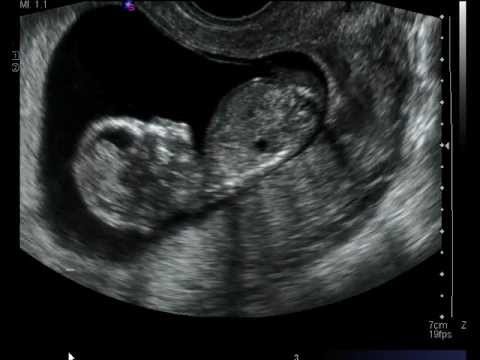

يمكن معرفة علامات الطفل المنغولي في السونار عن طريق فحص الشفافية القفوية للجنين، ويتم ذلك من خلال فحص الفقرات العنقية الخاصة به خلال الفترة بين الأسبوع 11 إلى الأسبوع 13 من الحمل.

ويركز هذا الفحص على مساحة صغيرة توجد بالنسيج الموجود بمؤخرة عنق الجنين والذي يطلق عليها اسم الطية القفوية، وقد كشفت الدراسات أن تلك البقعة تقوم بجمع السائل القفوي، وفي حالة إذا أظهرت النتيجة وجود كمية أكبر من السائل القفوي، فإن احتمالية اصابة الجنين بأمراض اختلال الكروموسومات مثل متلازمة داون تصبح أكبر.

يمكن لهذا الفحص أن يكشف عن العيوب الخلقية التي تكون مصاحبة لمتلازمة داون مثل: وجود عيب بالجدار الاذيني البطيني للقلب، أو وجود عيوب بالأمعاء الدقيقة، أو عدم وجود عظام الأنف، أو وجود قصر بعظم الفخذ.

عيوب سونار الحمل للكشف عن الطفل المنغولي

لا تعد نتائج سونار الحمل دقيقة بالشكل الكافي، حيث إن قابليته في تحديد الاصابة بمتلازمة داون عن طريق فحص السائل القفوي تمثل 75% من الحالات، ويستطيع السونار أن يكشف حوالي 58% من حالات العيوب الخلقية المصاحبة لمتلازمة داون والتي من أبرزها غياب عظام الأنف.

واحيانا يمكن أن يقوم السونار بإعطاء نتيجة إيجابية خاطئة تشير لاصابة الطفل بمتلازمة داون، ولهذا لابد من التأكد من خلال اجراء كافة الفحوصات الاخرى للحصول على نتائج أكثر دقة.